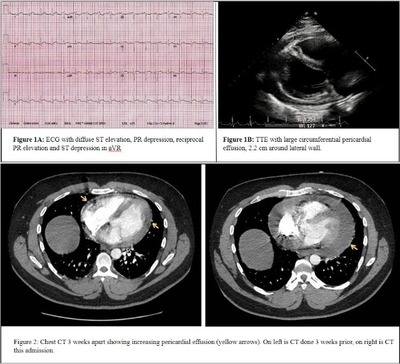

Case presentation: A 28-year-old male with history of psoriasis on secukinumab therapy presented with sharp, central chest pain, and progressive shortness of breath for 3 weeks. He was evaluated for similar chest pain 3 weeks prior; CT chest showed small pericardial effusion and he was managed with analgesics without improvement. This admission, he had tachycardia, and ECG showed sinus rhythm with diffuse ST elevation and PR depression (Figure 1A). Troponin I levels were normal and inflammatory markers were elevated. Transthoracic echocardiogram (TTE) revealed a large pericardial effusion without tamponade physiology (Figure 1B). CT chest confirmed large pericardial effusion, increased in size compared to CT done 3 weeks prior (Figure 2). He was diagnosed with pericarditis and started on ibuprofen and colchicine which improved his symptoms. Search for viral etiology including testing for COVID, influenza A and B, RSV, hepatitis and HIV were negative. Immunological workup for ANA and rheumatoid factor was negative. Thus, secukinumab was thought to be the likely culprit. Follow-up TTE in 3 months showed resolution of pericardial effusion.